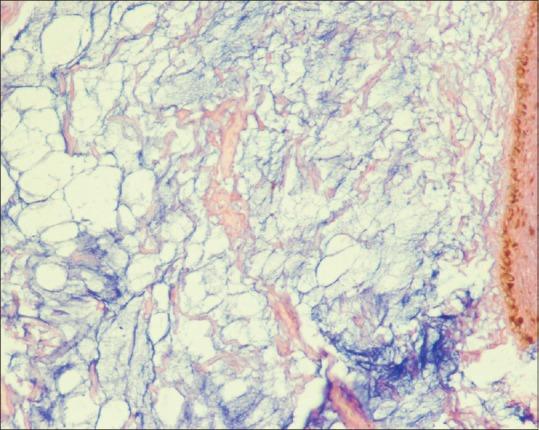

Cutaneous mucinoses refer to disorders with abnormal accumulation of mucin in the skin. Mucin is an amorphous material that is a part of the extracellular matrix in dermis. Cutaneous mucinoses could be primary or secondary. The latter is associated with systemic disorders such as autoimmune diseases, diabetes mellitus, paraproteinemia, or altered thyroid function. Here, we report an adult female patient with trauma-induced cutaneous focal nodular mucinoses on left-sided scapular region. Histology showed replacement of collagen bundles by mucinous deposits in superficial and mid-dermis. Mucinous substance was present in peri-eccrine location on Alcian blue staining.